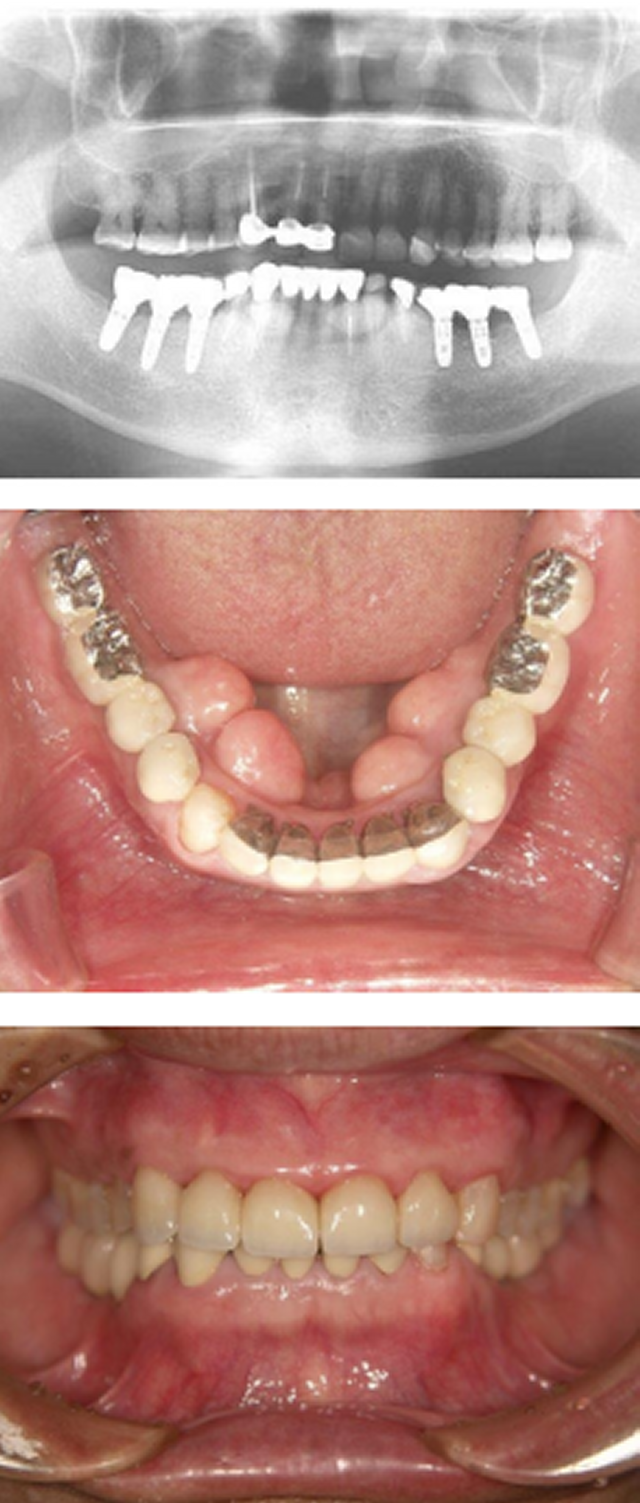

インプラント咬合改善症例

インプラント施術前

下あごの奥歯がなく、食いしばりが強いため前歯もすり減ってしまいました。

インプラント施術後

インプラントを6本埋入してかみ合わせも適当な高さに改善、前歯もセラミックをかぶせて見た目も改善しました。